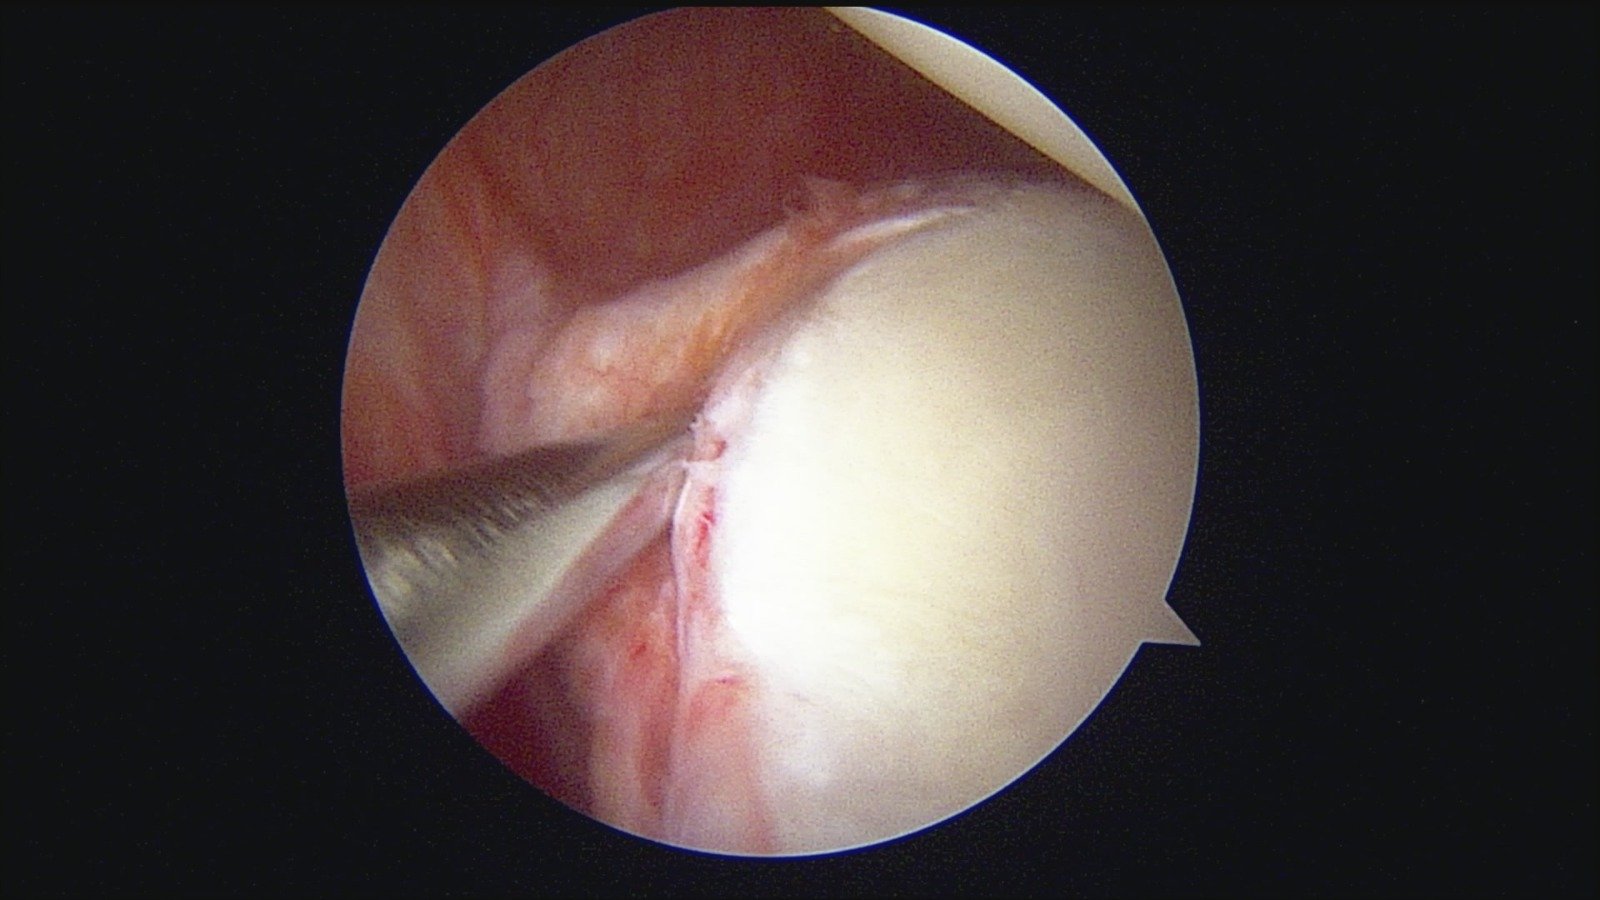

GalleryShoulder rotator cuff repair Meniscus root repair Meniscus repair Bankart repair for recurrent shoulder dislocation ACL reconstruction Machines Instruments